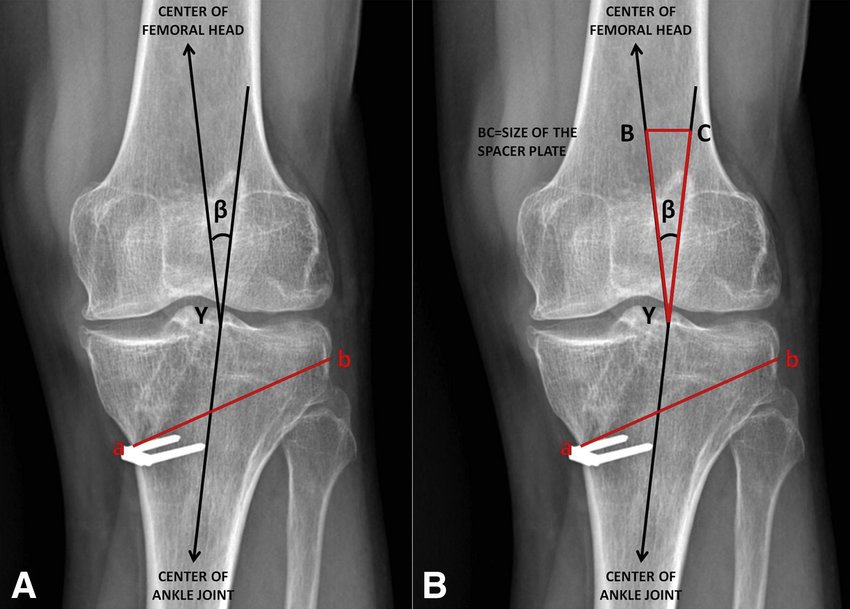

High tibial osteotomy is an orthopaedic surgical procedure which aims to correct a varus deformation with compartmental osteoarthritis. Since the inception of the procedure, advancements to technique, fixation devices, and a better understanding of patient selection has allowed HTO to become more popular in younger, more active patients hoping to combat arthritis. The idea behind the procedure is to realign the weight-bearing line of the knee. By realigning the knee, the force produced from weight-bearing is shifted from the arthritic, medial compartment to the healthy, lateral compartment. This decrease in force or load in the diseased part of the knee joint decreases knee pain and can delay the development or progression of osteoarthritis in the medial compartment. The general surgical technique includes either performing HTO alone or performing HTO in combination with ligament reconstruction. When deciding which treatment avenue to take, one must consider patient demographics, their predominant symptoms, and which ligaments, if any are involved. When ligaments are involved, but the ACL deficiency is chronic and pain is due to arthritis and malalignment, HTO alone should be sufficient.